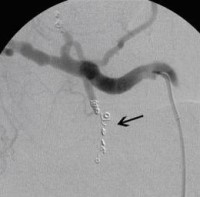

Postoperative abdominelle Blutungen bei chronischer Pankreatitis vor Embolisation der Art. gastroduodenalis mittels Metallspiralen (Coils)

(Bild 2 von 5)

Postoperative abdominelle Blutungen bei chronischer Pankreatitis nach Embolisation der Art. gastroduodenalis mittels Metallspiralen (Coils)

(Bild 3 von 5)